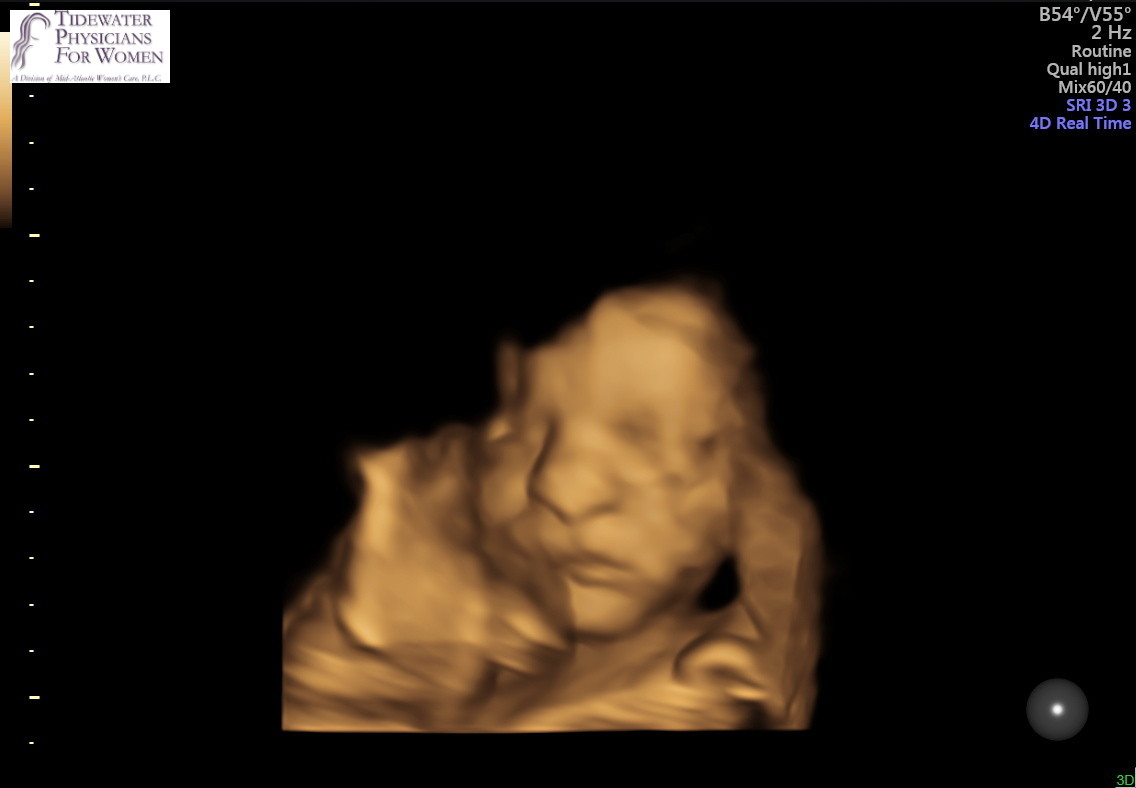

@alexxajams they only tried the 3D for a few minutes, and I think only to try to get a good picture for us. Not sure my regular OB even has a 3D one in their office